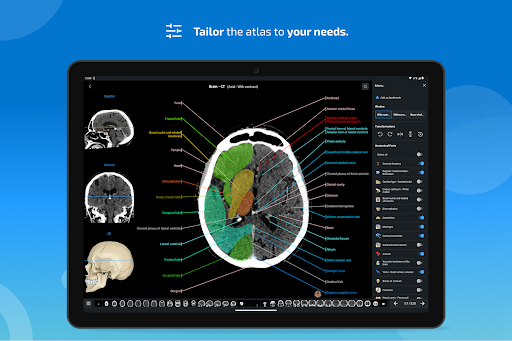

- Pilih label anatomi berdasarkan kategori

- Anda sekarang dapat menyembunyikan struktur satu per satu (tombol baru di dalam tampilan deskripsi) dan menampilkannya lagi di menu sebelah kanan